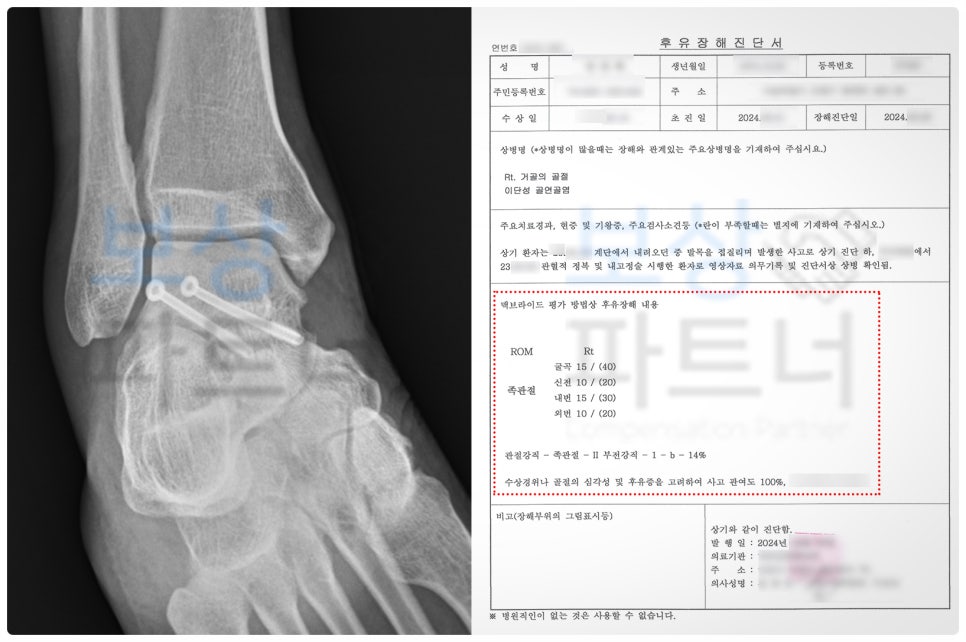

근로자의 손해액을 입증하여 청구하는 것 역시 재해자 본인에게 달려있습니다. 그러므로 손해액(위자료, 상실 수익액 등)을 산정하기 위해서는 노동능력 상실률(%) 평가가 필수입니다.

평가 방법은 '맥브라이드 후유장해 평가' 방식을 따라야 하는데요. 그런데 섣불리 개인이 주치의에게 요청하여 장해 평가를 진행한다면, 후유증상에 대한 기록이 온전히 담기지 않을 수 있습니다.

그럼에도 불구하고, 거골의 골연골염 손상 관련 의학적 기록과 유사 판례를 면밀히 검토하여 청구를 진행하였습니다.

청구 이후 수개월간의 분쟁 끝에 한시장해를 인정받을 수 있었고, 결국 근재보험에서 약 2,300만 원을 추가로 지급받게 되었습니다.